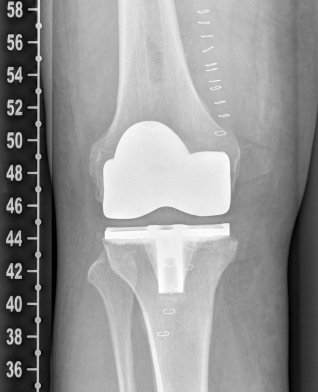

Example X-ray images before and after implantation of a Persona knee prosthesis with robot.

| b) nach Implantation der Knie-Totalendoprothese angefertigte Röntgenaufnahmen | |

With the robot-guided support, the artificial knee joint is then inserted with millimeter precision, and the required establishment of the straight leg axis in the knee joint as well as the correct rotations of the prosthetic components can then be ensured.